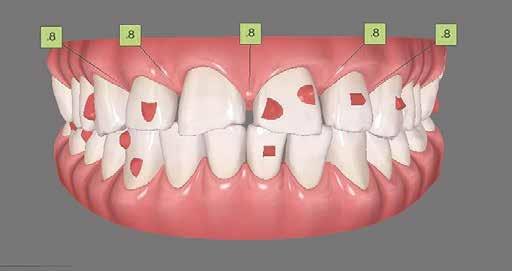

A 26 éves férfi páciens azzal a kéréssel kereste fel a rendelőnket, hogy a frontfogai esztétikusabb megjelenését szeretné elérni. A páciens jó általános egészségi állapottal rendelkezett, nem szenvedett allergiáktól és nem kellett rendszeresen gyógyszereket szednie. A páciens lehetőség szerint kerülte a fogai megmutatását. Rendkívül zavarónak találta a nagymetszői között, a középvonalnak megfelelően látható rést, a fogain látható kopási jeleket, valamint a fogai méretét is túl kicsinek találta. A szájüregi vizsgálat során megállapítottuk, hogy a nagymetsző fogai (11, 21) élharapásban vannak, valamint az alsó fogíven kismértékű torlódást észleltünk. A felső frontfogakon

(13-23) attrícióra utaló jeleket találtunk. A fogak kopása a nagymetszőfogaknak megfelelően volt a legkifejezettebb (1. ábra) . Az előbbiekben említett fogak (11, 21) ezen kívül némileg elfordultak, és jelentősebb méretű diasztéma volt köztük. A páciens Angle I.-osztályú állcsontrelációs helyzettel rendelkezett. A vizsgálat során feltűnt, hogy a páciens csak nagyon óvatosan mert mosolyogni (2. ábra)

A szájüregi vizsgálat során nem találtunk szuvas léziók jelenlétére utaló eltéréseket. A nagymetszőfogakon megfigyelhető jelentős mértékű kopás ellenére nem észleltünk craniomandibuláris diszfunkció jelenlétére utaló jeleket. A vizsgálat befejezését követően a pácienst tájékoztattuk a különböző kezelési lehetőségekről. Az esztétikai megjelenés javítása érdekében először egy alignerekkel végzett fogszabályzó kezelés elvégzését, majd a harapási helyzet optimalizálását követően a felső frontfogai kompozittal történő direkt felépítését vagy héjakkal történő ellátását (pl.: non-prep héjak) javasoltuk (3. és 4. ábra).

A fogazat minimálinvazív módon készített héjakkal történő ellátásához a fogaknak olyan pozícióban kell lenniük, amely lehetővé teszi az esztétikai megjelenés additív eljárások alkalmazása mellett történő optimalizálását.1. ábra: Kiindulási állapot. A felső nagymetszőfogak élharapásban vannak. 2. ábra: Az orthodonciai kezelés megkezdése előtt készített intraorális felvétel. A páciens csak óvatosan mer mosolyogni. 3. és 4. ábra: Digitálisan megtervezett kezelés.